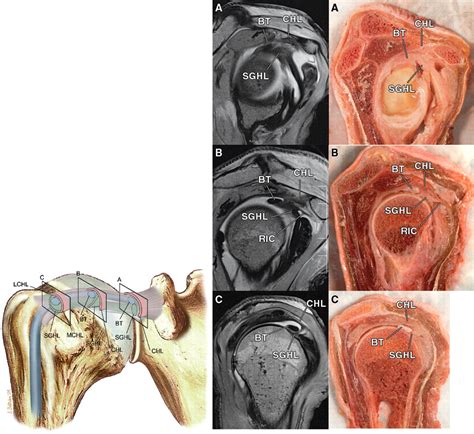

The rotator cuff interval is a triangular space located in the anterior-superior aspect of the shoulder joint. It is bordered by the superior margin of the subscapularis tendon and the anterior margin of the supraspinatus tendon. The base of this triangle is formed by the coracoid process, while the apex extends toward the intertubercular groove of the humerus. Several vital structures traverse this interval, playing a pivotal role in shoulder stability:

• Coracohumeral Ligament (CHL): A primary stabilizer that prevents inferior translation of the humeral head.

• Superior Glenohumeral Ligament (SGHL): Provides resistance to external rotation and helps secure the humeral head.

• Long Head of the Biceps Tendon (LHBT): Travels through the interval before entering the joint space, acting as a dynamic stabilizer.

Because this area lacks the thick, muscular coverage found in other parts of the cuff, it is inherently weaker. This anatomical vulnerability makes it a frequent site for injury, particularly in patients who perform repetitive overhead movements or suffer from chronic shoulder instability.